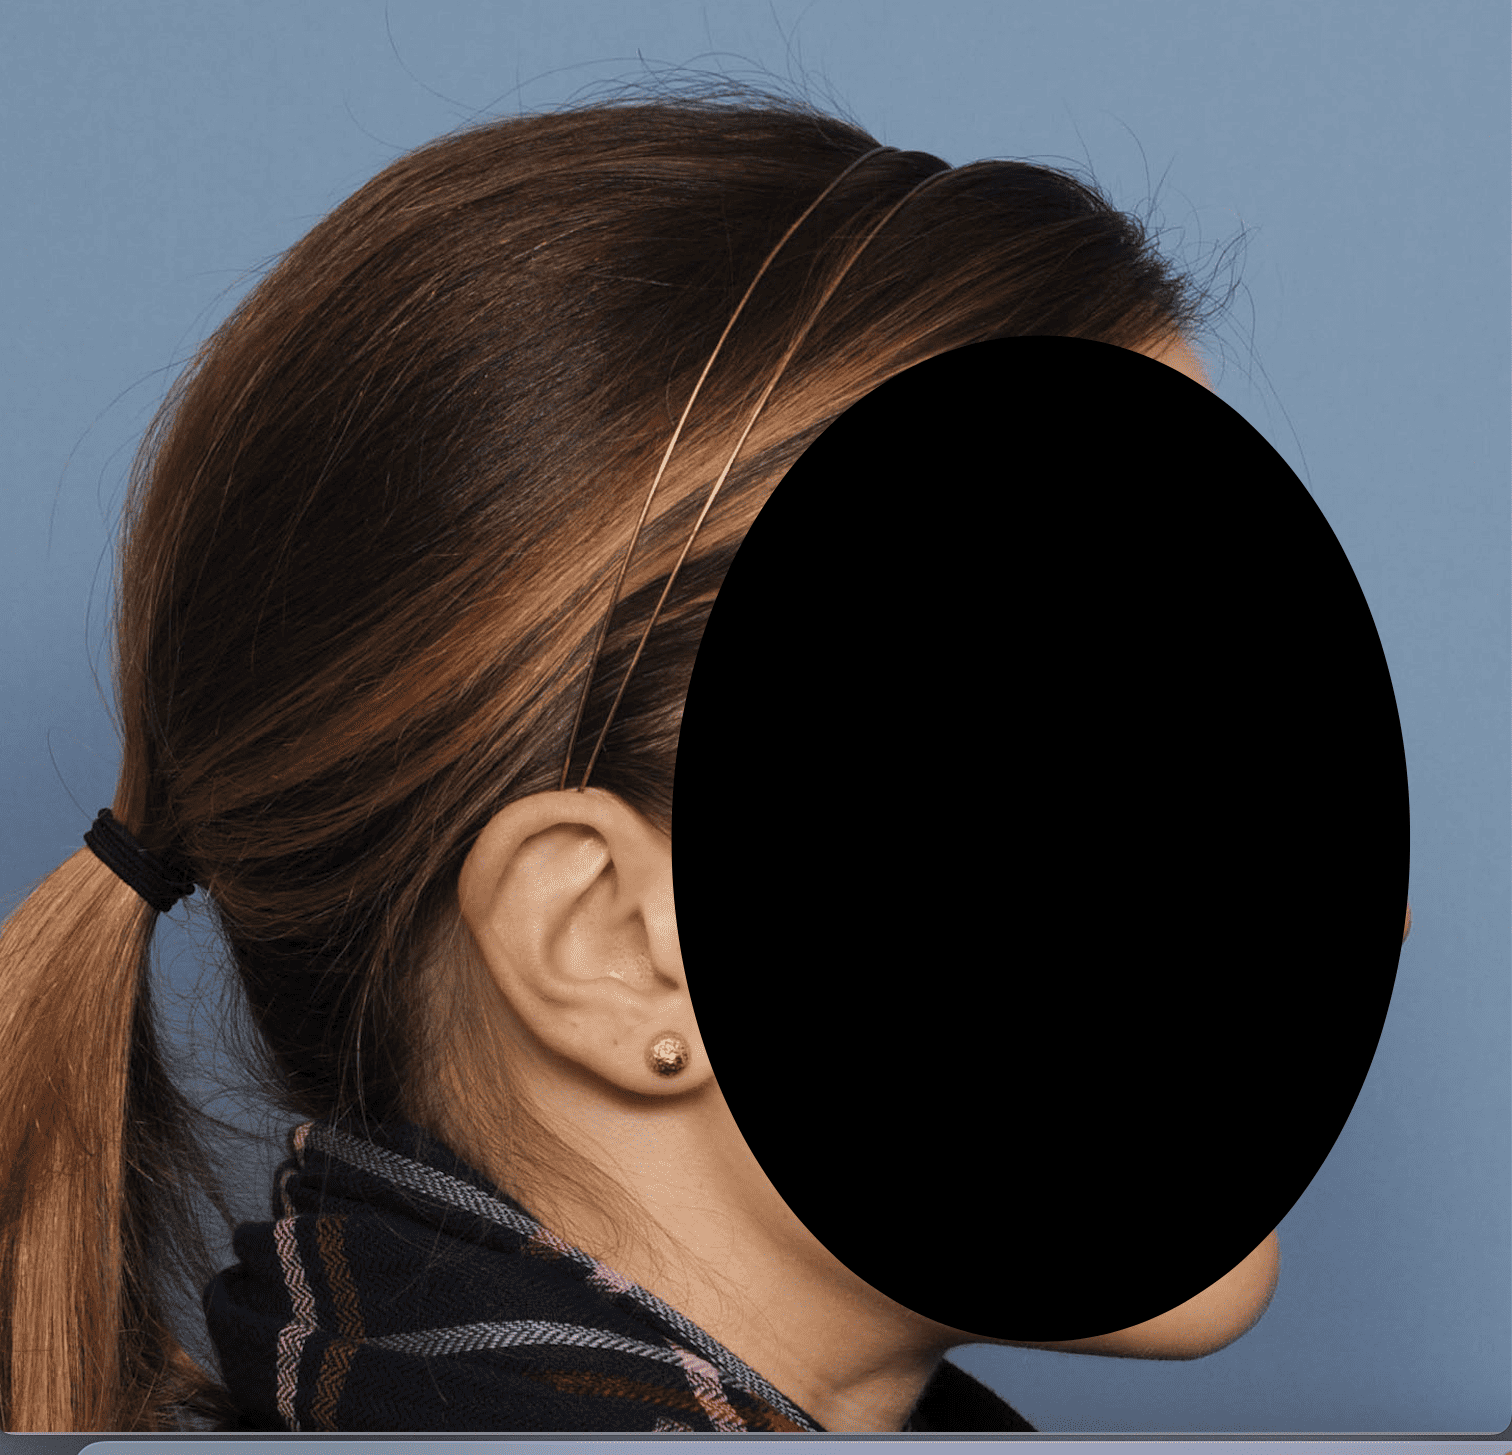

Desire for a higher and more prominent crown of the skull.

Crown of skull augmentation using a custom skull implant.

Desire for a higher and more prominent crown of the skull.

Crown of skull augmentation using a custom skull implant.